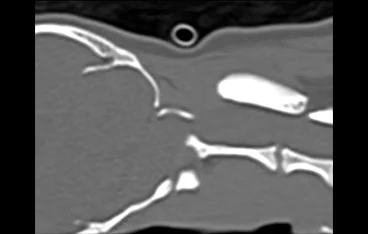

환축추아탈구(AAI)

AAI stabilization(screw + PMMA)

• AAI